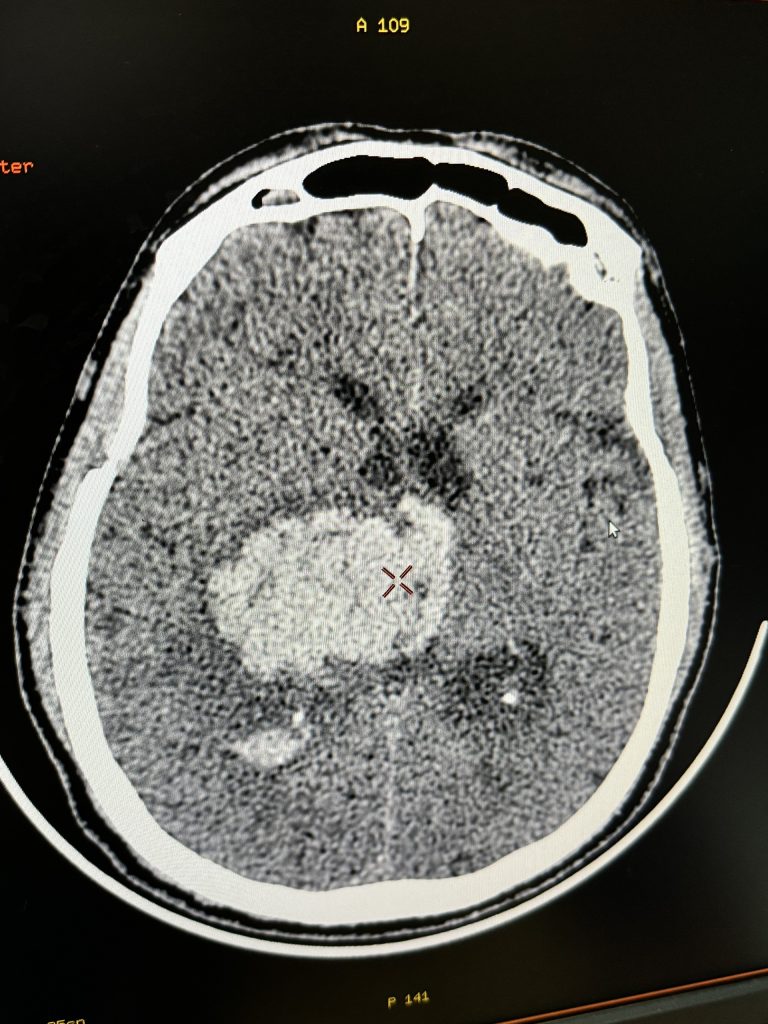

Người bệnh sau khi thăm khám và thực hiện các kỹ thuật cấp cứu: đặt nội khí quản, ống thông dạ dày, ống thông bàng quang, được chỉ định làm các cận lâm sàng cần thiết. Kết quả chụp CT cho thấy hình ảnh có ổ chảy máu nhu mô não nhân xám thần kinh trung ương phải: kích thước 37x27x35mm gây phù não xung quanh và đẩy lệch đường giữa sang trái gần khoảng 11mm gây tràn máu vào hệ thống não thất.

Sau 9 ngày điều trị, ông T được chụp lại CT sọ não kết quả cho thấy ổ chảy máu ở nhu mô kích thước nhỏ lại có dấu hiệu hóa dịch. Sau đó người bệnh được các bác sỹ hội chẩn, thống nhất tiến hành mở canuyn khí quản để thông khí xuống phổi tốt hơn, giảm nguy cơ tắc đờm ở đường thở và khi cai máy thở sẽ giảm công hô hấp cho người bệnh dễ thở hơn.